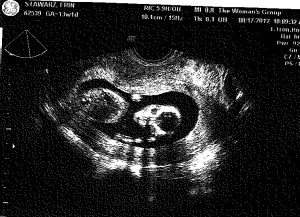

Baby S – 13 weeks